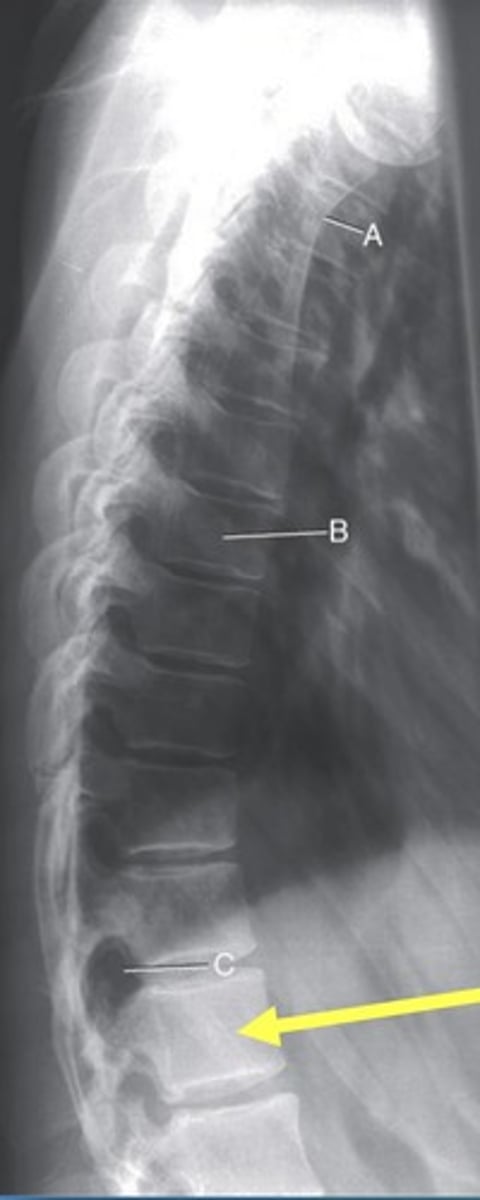

T3-4 intervertebral disk space

B.

T4 transverse process

C.

T5 Pedicle

D.

T7 spinous process

E.

T11 costovertebral joint

F.

T11 inferior articular process

G.

T12 superior articular process

H.

L 1st rib

I.

L 3rd posterior rib

J.

L 9th posterior rib

K

T3 body

A.

T12 floating rib

L